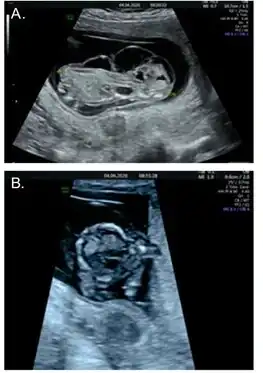

- ↑ 3.0 3.1 3.2 3.3 3.4 Lazebnik, Noam; Cohen, Leslie (2015-07-01). "Prenatal diagnosis and findings of tetrasomy 9p". Journal of Obstetrics and Gynaecology Research. 41 (7): 997–1002. doi:10.1111/jog.12706. ISSN 1447-0756. PMID 25944096.